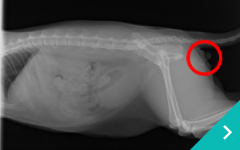

ステント治療

ステント

治療